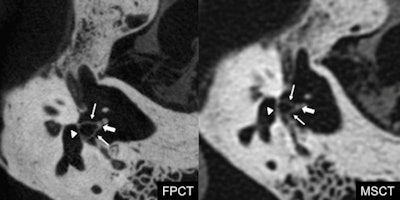

Footplate of the stapes (arrowhead), anterior and posterior crus (arrows), and head of the stapes (thick arrow). Flat-panel CT depicts all the components of the stapes better compared with multidetector CT, thanks to its higher spatial resolution and smaller field-of-view, which allows a magnified view. Courtesy of Dr. Giorgio Conte.Two neuroradiologists with three years and eight years of experience in otoradiology independently evaluated depiction of 30 anatomical structures in both the flat-panel CT and MDCT of the 15 specimens in a randomized order. These anatomical structures of the external, middle, and inner ear were evaluated with a 0 to 2 score: 0 = the structure could not be visualized; 1 = the structure could be identified but was not well-delineated from the surrounding tissues, or some parts of the structures were poorly identified; and 2 = the structure was well-visualized and delineated from the surroundings in all of its parts. Meanwhile, they used an anthropomorphic Rando Alderson phantom (Rando Alderson Research Laboratories, New York City, New York) to estimate the radiation dose.

While MDCT yielded higher signal, lower noise, higher signal-to-noise ratio (SNR), and fewer artifacts, flat-panel CT showed a significantly higher image quality overall score compared with MDCT (p < 0.0017 after application of the Bonferroni correction for multiple testing). Specifically, FPCT provided better images of 10 structures: the bone marrow of the malleus, the incudomalleolar joint, the anterior crus of the stapes, the posterior crus of the stapes, the footplate of the stapes, the tendon of the tensor tympani muscle, the stapedius muscle, the lateral ligament of the malleus, the modiolus, and the greater petrosal nerve (all p < 0.0017 after application of the Bonferroni correction for multiple testing). Furthermore, no structure was depicted better with MDCT than with flat-panel CT.